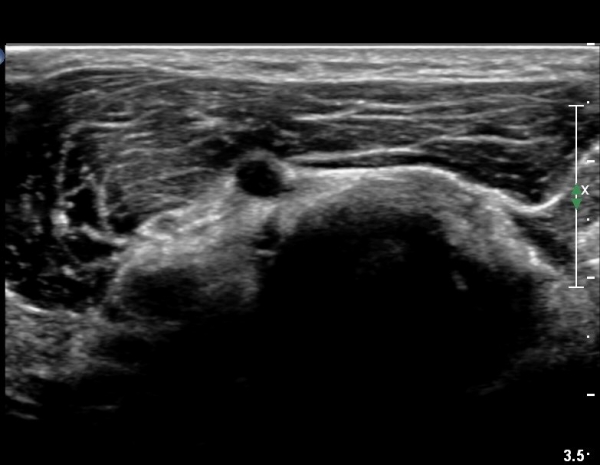

ŽÃËÀÚ¸¦ ¾à°£ ¸»´ÜÀ¸·Î À̵¿ÇÏ´Ï(¿ä°ñµÎ ºÎÀ§) Å« ³¶Á¾ÀÌ º¸ÀÌ°í ³¶Á¾ÀÇ ¿ÜÃø¿¡ Èİñ°£½Å°æÀÇ ¾Ð¹ÚÀÌ °üÂûµÈ´Ù(»çÁø 2). ³¶Á¾Àº ¿ä°ñµÎ¿¡¼­ ¿ä°ñºÎÀ§±îÁö À§Ä¡ÇØ ÀÖ´Ù(»çÁø 3)

ŽÃÊÀÚ¸¦ ȸ¿Ü±Ù ºÎÀ§±îÁö À̵¿ÇÏ´Ï ³¶Á¾Àº °í³ªÂûµÇÁö ¾Ê°í µÎ ȸ¿Ü±Ù »çÀÌ¿¡ Àִ  Èİñ°£½Å°æ

ºÎÁ¾ÀÌ °üÂûµÈ´Ù(»çÁø 4).

Èİñ°£½Å°æ Á¾´Ü¸é°Ë»ç¿¡¼­ ³¶Á¾°ú ÀÎÁ¢ÇÏ¿©  À§Ä¡ÇÑ Èİñ°£½Å°æÀÇ ºÎÁ¾ÀÌ °üÂûµÈ´Ù(»çÁø 5, 6).